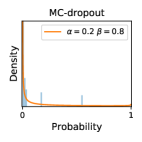

5.1 Distribution of Uncertainty Scores

Distribution of Uncertainty Scores Across Different Severity Levels As explained in Section 3, each uncertainty metric essentially defines an order/ranking among the data points. We conducted an analysis to better understand what data will be assigned high uncertainty under a particular uncertainty metric . Picking out the highest ranked data points (), we calculated the ratio of data points from each SL. Figure 4 summarizes the results as box plots for the Kaggle-DR and the Messidor-2 datasets; additional detailed statistics can be found in Table S.1 in the supplementary materials. From the plot and table, SL1 & SL2 examples account for a higher proportion among the top-ranked uncertain examples across the three ensemble methods. This finding matches our intuition that incipient disease examples (SL1 & SL2) are more likely to be considered uncertain by ensemble methods due to their ambiguity.

In contrast, the MC-dropout method showed the worst overall performance among the three, as it can be seen from the high ratios of SL0 examples among the uncertain negatives in Figure 4. The histograms in Figure 2 provides another perspective to look into the phenomenon, where a decent proportion of MC-dropout model’s predictions on SL0 inputs entailed low confidence (far from 0 or 1), which from another angle explained why MC-dropout was less specific in terms of lower FNP; many no-DR inputs (i.e. SL0) were erroneously assigned high uncertainty by MC-dropout models.

It is still an open question why the evaluated MC-dropout networks signaled relatively high uncertainty on SL0 & SL3 & SL4 data that are less likely to be ambiguous. We conjecture that much of the “uncertainty” indicated by disagreement among test-time dropout samples actually reflects the stochastic nature of dropout networks rather than the real decision uncertainty associated with the data. It is worth noting that the MC-dropout model we evaluated was not weak per se; they all achieved above Area Under Curve (AUC) scores on test sets. The weakness of individual test-time samples (which explains their low-confidence predictions on SL0 & SL3 & SL4) might have been hidden when they are aggregated into an ensemble—a well-known advantage of ensemble learning. Our results suggested that the uncertainty information given by implicit ensemble methods such as MC-dropout and TTA might not be as reliable as that from explicit ensemble approaches (e.g., stacking ensembles). Similar findings on MC-dropout can be found in some previous papers [1].